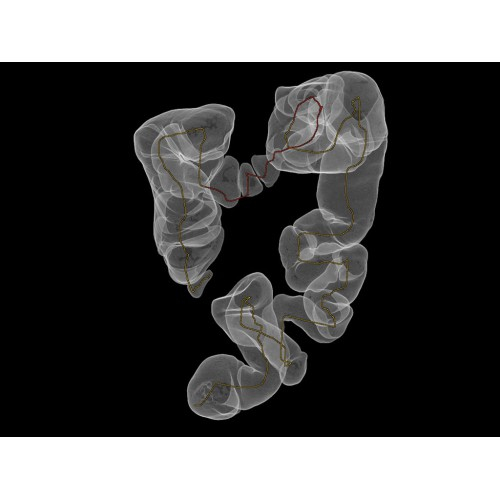

Компьютерный томограф GE Brivo CT385 представляет собой современное диагностическое оборудование, сочетающее высокую точность исследований с повышенным комфортом для пациентов. Этот аппарат открывает новые возможности для детальной визуализации анатомических структур.

Позволяет проводить комплексные исследования всех анатомических зон, включая нейровизуализацию, ангиографию, исследования органов грудной и брюшной полости. Особенно эффективен для раннего выявления онкологических заболеваний.

Специализированные исследования